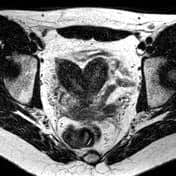

Bicornuate uterus:

- Early pregnancy loss and cervical incompetence

- Incomplete fusion of paramesonephric duct

- Associated longitudinal vaginal septum, abnormal renal tract

- Bicornuate uterus: Divided uterus

- Septate uterus: An angle of less than 75° between the uterine horns is suggestive of a septate uterus, and an angle of more than 105° is more consistent with bicornuate uteri.